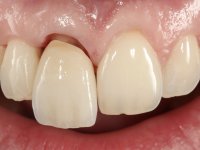

The patient did not like the upper right central incisor. I wanted to improve the smile because the “front tooth was dark and narrow”.

The treatment began with the placement of an intraradicular post and the creation of a new composite resin restoration. This procedure was performed with a surgical approach that allowed the remaining margins to be completely exposed, which were shown to be at a very infra-gingival level. Simultaneously, the periodontal pocket was curetted and root scaling and root planning of adjacent teeth were performed. Two months after this first intervention, the making of the crown began. A pre-print on silicone was performed to make a temporary crown with dual-cured composite resin. Gingival retraction was performed using the technique of kaolin paste compressed by the provisional crown. The impression was made using the double-mix technique with double viscosity with quick-setting silicone. In the laboratory, a crown with a ceramic-coated Zr infrastructure was made. The crown slightly overlapped tooth 12, allowing a dimensionally mimicry of the symmetrical tooth. Its fit was confirmed and approved by the patient; it was definitively cemented with resin-reinforced glass ionomer cement.